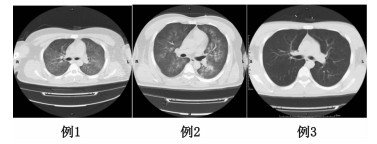

3例患者均为男性,年龄21~45岁,平素体健,化工厂工人。工作中接触泄漏的有机氟气体八氟异丁烯后咳嗽气喘约8 h于2014年11月13日来我院急诊 (患者均为车间工作,具体接触原因不详,大约接触7 h后首先出现咳嗽症状)。来院时均有不同程度的胸闷、气急,并且开始出现恶心、呕吐等症状。查体:GCS 14~15分,HR 110~140次/min,平均动脉压 (MAP) 65~75 mmHg (1 mmHg=0.133 kPa),呼吸 (R) 35~40次/min,双肺呼吸音粗,可闻及广泛湿啰音,心律齐。血气分析:PCO2 30~39 mmHg,PO2 51~73 mmHg,氧合指数 (PO2/FiO2):150~195 mmHg,肺CT示:两肺片状模糊影,广泛渗出 (图 1)。根据职业性急性有机氟中毒诊断标准 (GBZ66-2002)[6]和ARDS柏林标准[7-8]诊断:急性有机氟气体吸入中毒、急性呼吸窘迫综合征 (ARDS)。均按分诊分级标准分为Ⅰ级,经绿色通道收入重症监护室 (intensive care unit, ICU),首日APACHEⅡ评分为19~26分。24 h后复查肺CT进展迅速 (图 2)。

图 1 3例患者来院时肺CT检查结果